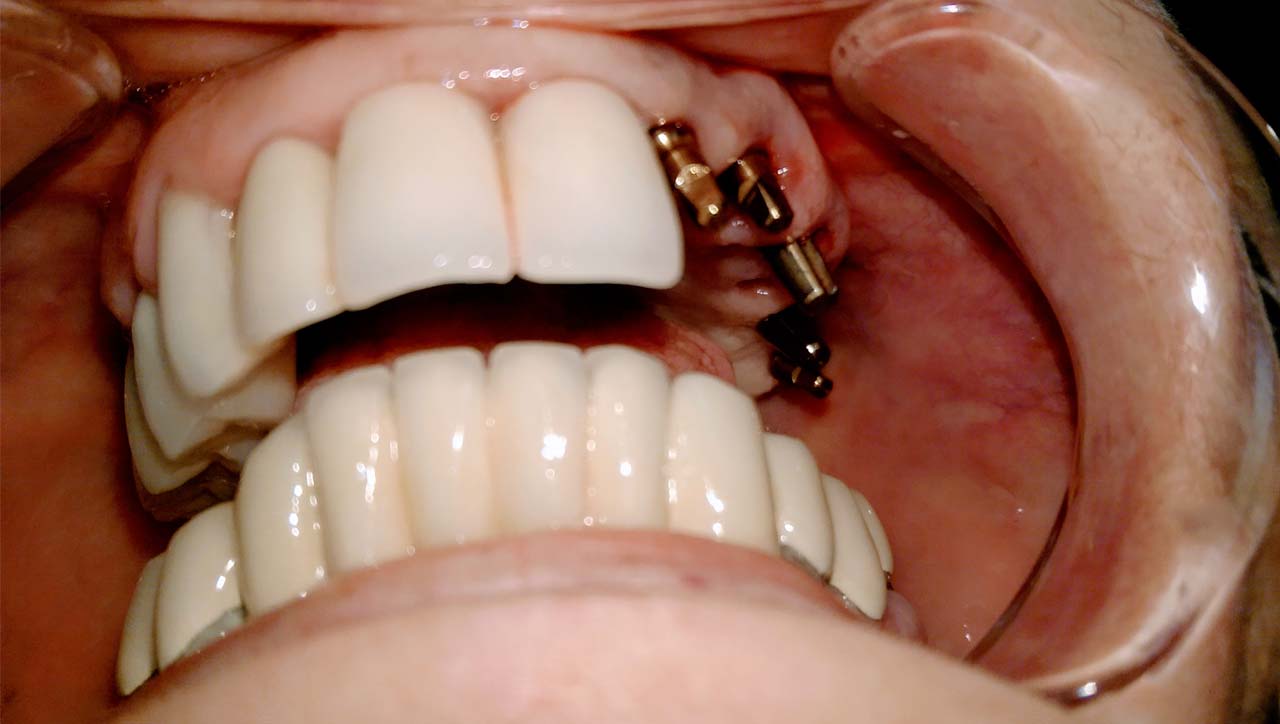

Teljes alsó,felső állcsont helyreállítása azonnal

terhelhető implantátumokkal és porcelán hidakkal.

Rágófunkció esztétikus helyreállítása azonnalterhelhető svájci IHDE implantátumokkal és porcelán koronákkal.

A régóta fennálló foghiány és a mozgó fogak miatt a páciens nem tudott jól rágni és harapni, illetve mosolyogni sem mert már jó ideje. A leggyorsabb és a legesztétikusabb megoldás az ilyen esetekre az IHDE azonnal terhelhető implantátumok behelyezése, és az azokra rögtön elkészített porcelán koronák elkészítése.

A teljes munka - az implantáció, a végleges koronák elkészítése - 5 munkanapot vett igénybe.

A mozgó, törött fogakon álló hidat a fogakkal együtt eltávolítottuk.

A fogak helyére, és a stratégiailag jó csontállományú hátsó területre azonnal behelyezett implantátumokra 3 nap múlva elkészítettük az esztétikus, azonnal terhelhető ideiglenes hidat.